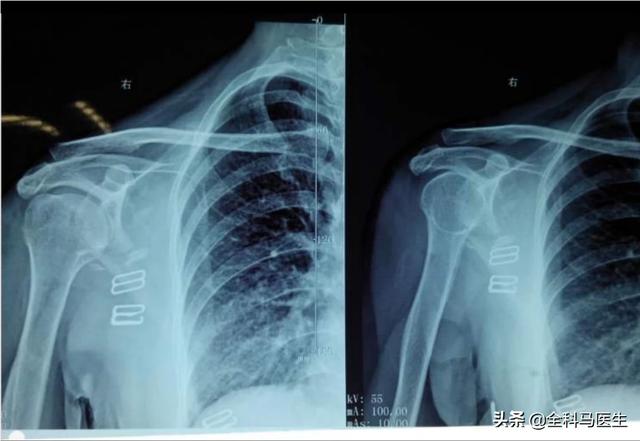

あるいは頸椎の適切な検査を行う。こういう状況にある人は多い。頸椎は湾曲が大きく変化する傾向があり、まっすぐになったり反動がついたりする。また、頚椎の湾曲が著しく変化している場合、頚椎周囲の筋膜も過緊張を起こし、トリガーポイントが形成される。

●硬化.医師の診察、筋肉超音波検査、頚椎のレントゲン検査の結果、問題があることが判明した場合治療はまだ保守的だ。可能筋肉の痙攣を和らげる内服薬クロルゾキサゾンなどの薬で、患者の症状を改善し、また、次のような治療も行う。鎮痛のための非ステロイド性抗炎症薬の内服または外用さらに、ツェ博士は次のように勧めている。鍼治療とマニピュレーション謝先生もひどい首、肩、背中の筋膜炎を経験したことがありますが、数回の鍼治療と操体法を受けた後、症状はとてもよく緩和されました。肩や背中の痛みがひどかったとき、操体法の先生が10分弱操体治療をしただけで、肩や背中の張りが50%くらい消えたのを今でも覚えています。

また謝医師は、肩甲骨の周辺に痛みが現れるものの頚椎の治療に関しては、気を抜くことはできない。頸椎は適切な位置にある鍼治療、手技療法、理学療法(マイクロ波、干渉点治療などまた、肩甲骨周辺の痛みを和らげるのにも役立つ。